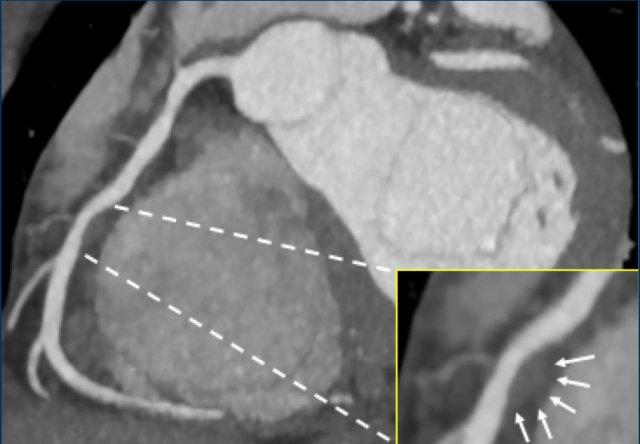

Same patient. First, study the CTA image.

How would you describe the findings?

The coronal image shows a central low-attenuation area around the lumen

of the LAD.

This low-attenuation area is surrounded by a higher attenuation

area.

This finding is the earlier discussed napkin-ring sign, which is a high-risk

plaque feature.

This patient classifies as CAD-RADS 4A/P1/HRP.

Continue with the next images of the same patient…

Same patient.

Double-oblique (A) and volume-rendered (B) images of the LAD showing the

location and the length of the plaque.

Also, the stenosis in the D2 branch of the LAD can be appreciated on the volume

rendered reconstruction.

Due to the degree of stenosis and the presence of napkin-ring sign (visible on

axial images) this patient underwent ICA where the presence of severe stenosis

was confirmed.